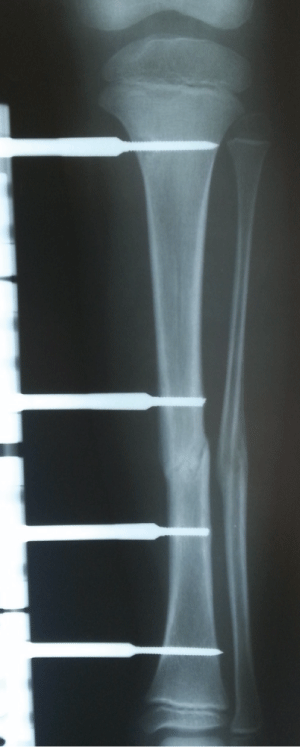

A 7-year old male patient presented at hospital after being struck by a motor vehicle and the first examination determined a Grade 1 open tibia fracture. The patient underwent surgery and an LRS-type external fixator was applied with 4 hydroxyapatite covered Schanz screws of 3mm diameter (Figure 1). With polyclinic follow-up examinations, union was observed in the fracture in the 6th week (Figure 2).